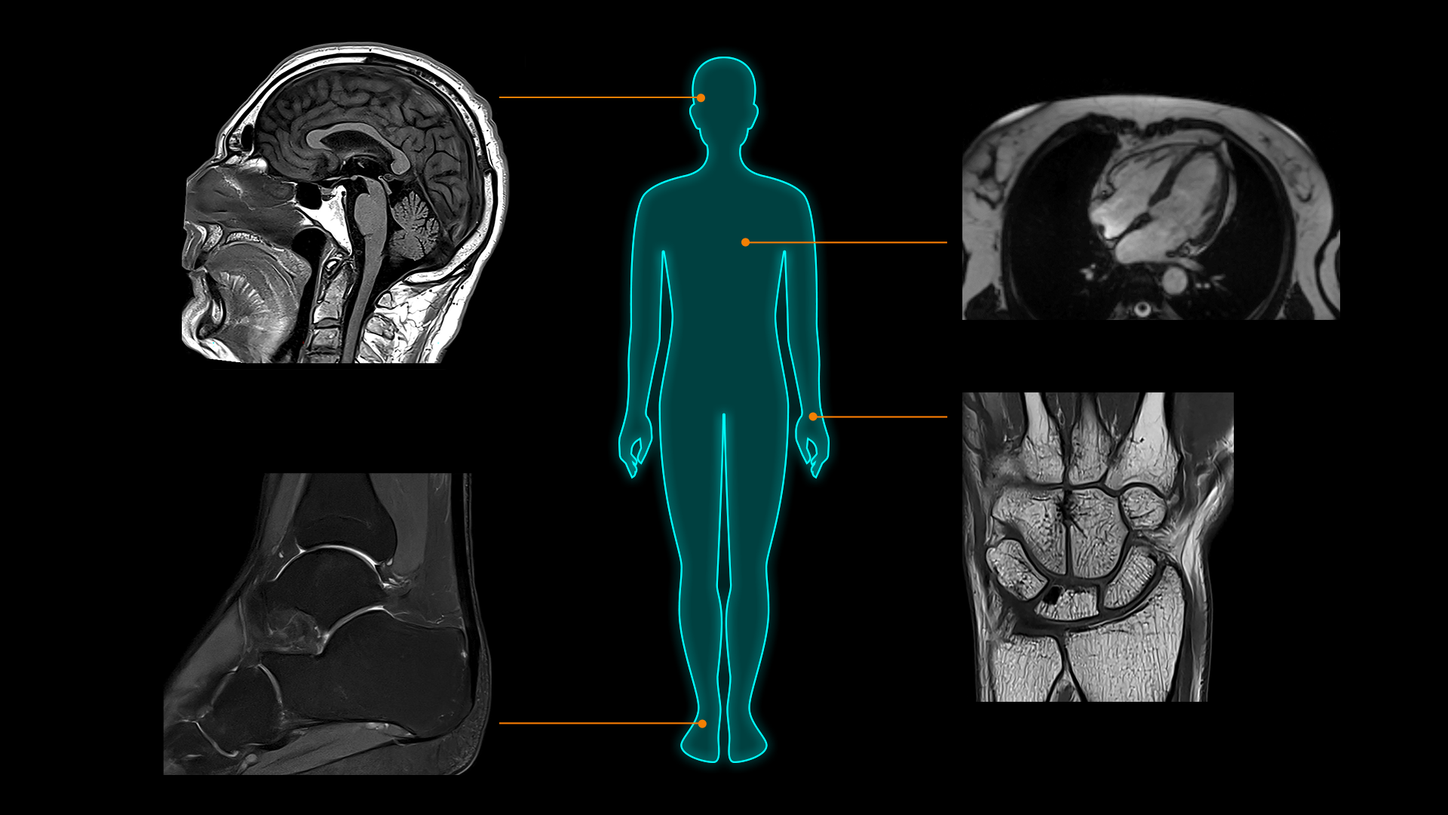

Clinical excellence from head to toe​

MAGNETOM Flow. Platform is designed to deliver highest-quality imaging for every clinical discipline. From routine imaging and screening to advanced imaging, from head to toe and from cardiac to oncology cases, it is planned to adapt to a wide range of imaging needs. Regardless of the type of institution, throughput demand, or clinical specialty, MAGNETOM Flow. Platform will empower you to achieve clinical excellence.